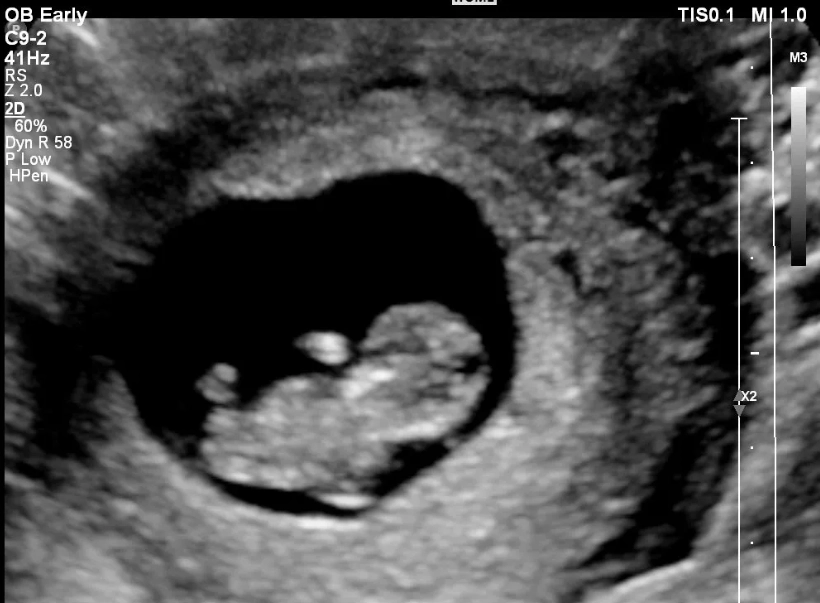

For many, the fog starts to lift around weeks 12-13. Nausea may begin to ease. You might get a surge of energy. And this is the prime window for a crucial check: the nuchal translucency (NT) scan, usually combined with blood tests (the first trimester screening). This scan, done between weeks 11 and 13+6, checks for certain chromosomal conditions. Scheduling this on time is one of the most important logistical steps of month three.

The Must-Do Appointment: If you haven't had your first prenatal visit, you're overdue. If you have, month three is often when you have your second visit. The headline act is the nuchal translucency ultrasound. It's not just a screening test; for many parents, it's the first time the baby looks like a real baby on screen, wiggling around. It's a powerful moment. You can find detailed guidelines on what this screening entails from authoritative sources like the American College of Obstetricians and Gynecologists (ACOG).

- Schedule & Attend Your NT Scan: Call your clinic. The timing is strict (11-13+6 weeks), so don't delay.